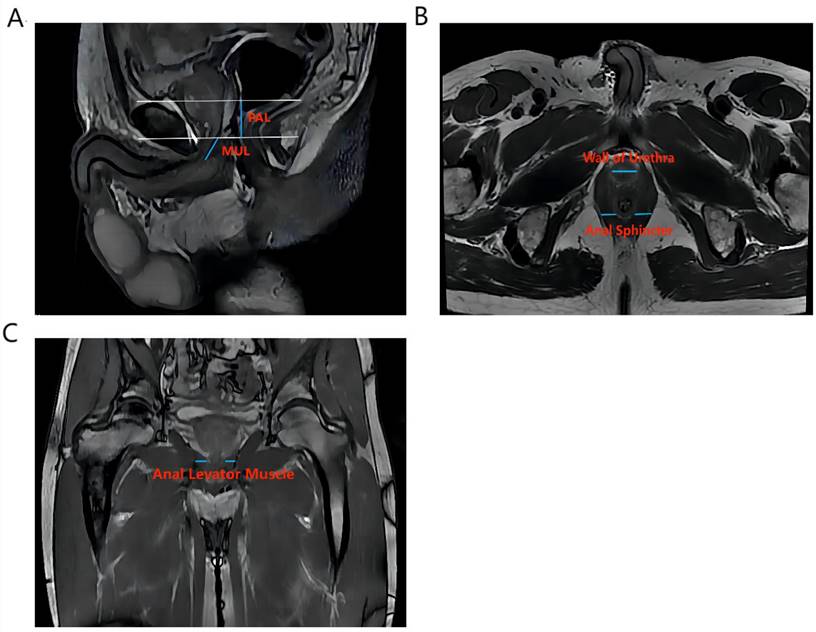

Vertical plane (Figure 1A): membrane urethra length (MUL), membrane urethra angle, prostate length, pubic symphysis-prostate apex length (PAL).

Figure 1

The main measurement indicators of anatomical structure on all T2-weighted images of patients. Figure 1A shows an example of a sagittal parameter on preoperative MR image; Figure 1B shows an example of a preoperative axial plane parameter; Figure 1C shows an example of a preoperative coronal parameter. PAL: pubic symphysis‒prostate apex length; MUL: membranous urethral length

Axial plane (Figure 1B): Thickness of the left/right musculus obturator internus, prostate height, prostate width, distance between the outer/inner edges of the anal levator muscle, transverse membranous urethra thickness, left/right anal sphincter thickness, and thickness of the urethral wall.

Coronal plane (Figure 1C): left/right anal levator muscle thickness